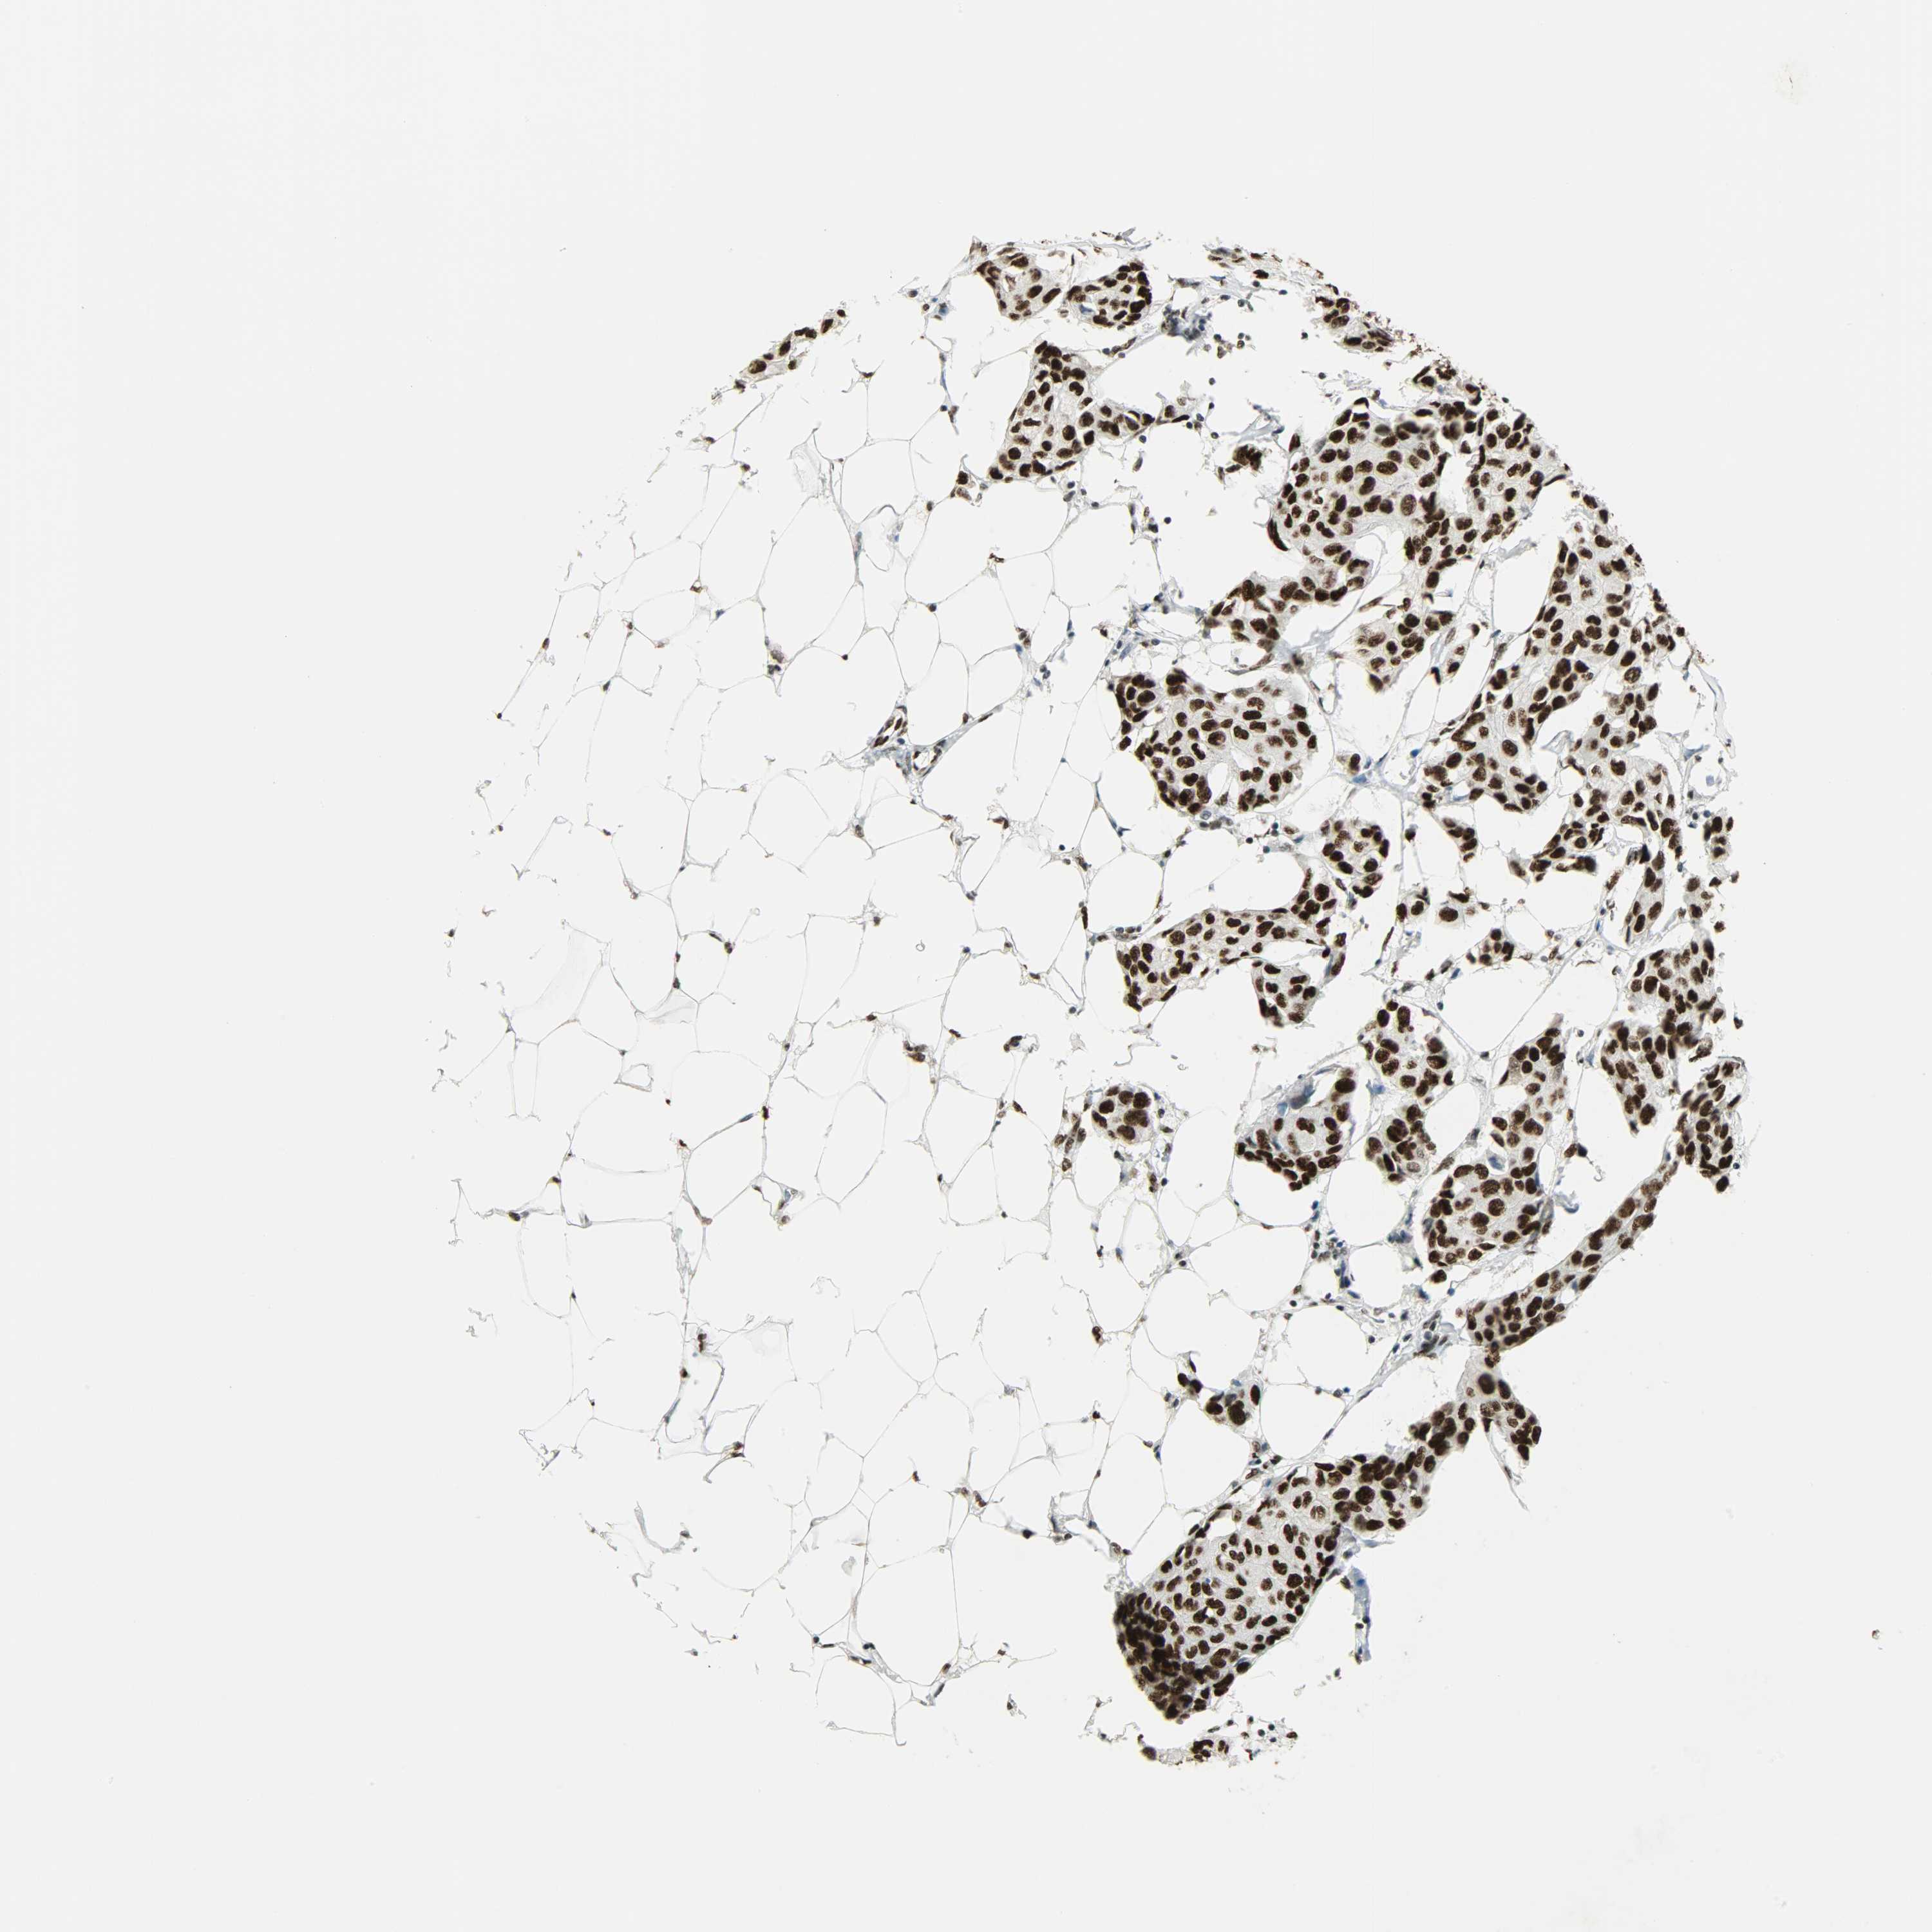

CANCER BREAST CANCER Show tissue menu

BRCA TCGA BRCA VALIDATION PROTEIN EXPRESSION

Breast cancer

Human cancer

Breast invasive carcinoma